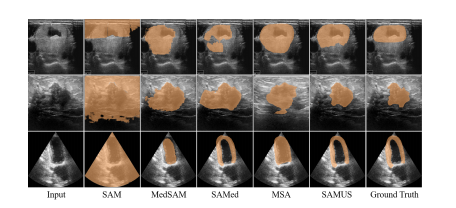

Figure 5: Qualitative comparisons between SAMUS and foundation models. From top to bottom are examples of seg menting thyroid nodule, breast cancer, and myocardium.

图5:SAMUS与基础模型之间的定性比较。从上到下分别是分割甲状腺结节、乳腺癌和心肌的示例。